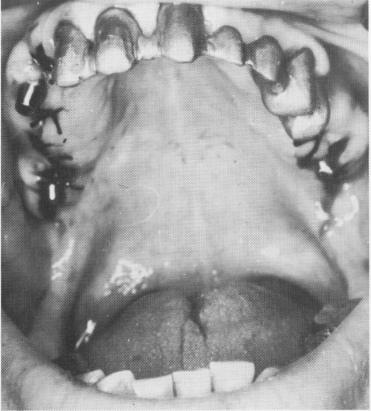

Fig. 11-82. The healed implant sites and the healing tissue around the prepared teeth.